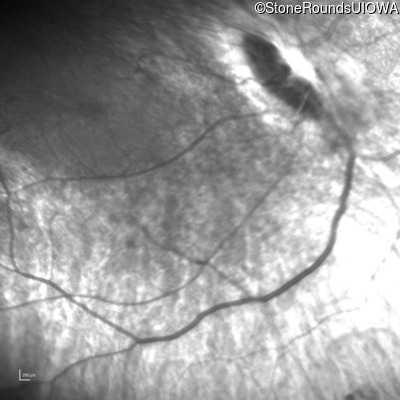

Infrared Fundus Photograph - Right - Light Perception

Exemplar